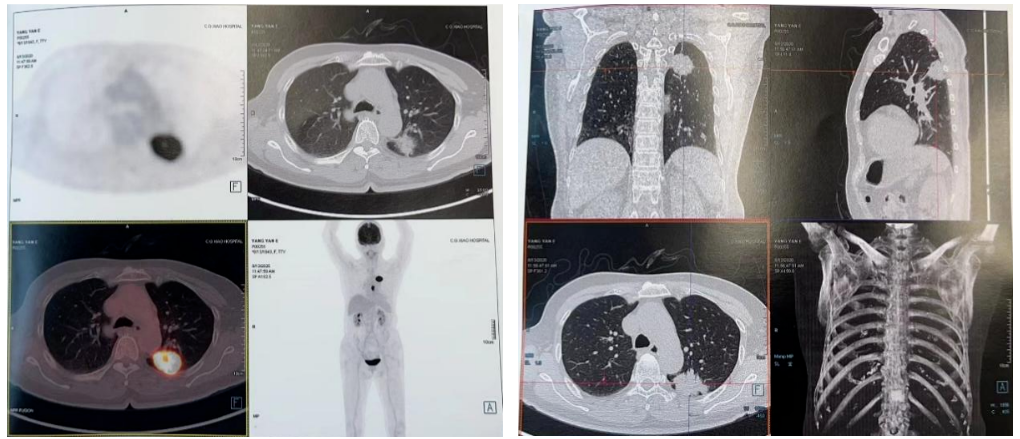

PET-CT(2020-08-13):食管胸下段管壁不均匀增厚,见放射性摄取增高,大小约18×14×27mm,SUVmax 14.6,符合食道癌表现。右侧肺门及纵隔(4R、5、7区)可见多个稍肿大淋巴结,最大约8×5mm,考虑炎性淋巴结可能性大。

左肺上叶尖后段团块状密度增高影,PET见放射性摄取增高,大小约40×29×31mm,SUVmax 28.0。病灶跨越左侧斜裂胸膜生长,密度均匀。左肺上叶胸膜下可见多发微小结节状密度增高影。建议治疗后复查,必要时活检排外恶性肿瘤的可能。

2021-10-28外院PET-CT:原食管胸下段管壁高代谢灶较前缩小,放射性较前减低,现大小约15×17×17mm,SUVmax 3.1,考虑为治疗后改变。左肺上叶团块状高代谢灶较前缩小,放射性摄取较前减低,现大小约25×18mm,SUVmax 2.1,考虑为治疗后改变。

2022-03-28 PET-CT:1、食管癌放化疗后,食管胸中段管壁不规则增厚伴结节状代谢增高,与上次(2021-10-28)PET/CT检查对比,病灶代谢较前明显增高,考虑为肿瘤复发病灶。2、左肺癌放疗后及靶向药治疗后,原左肺上叶团块状高代谢“肿瘤灶”,现范围较前稍缩小,代谢较前稍减低,考虑为治疗后改变(肿瘤完全活性受抑,伴少许炎性反应可能)。